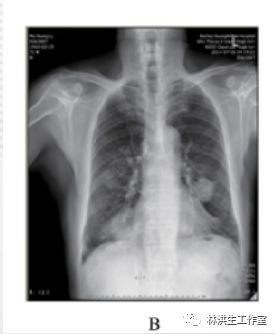

B:2014 年 7 月 26 日复查,经治疗显示双肺肿物缩小;